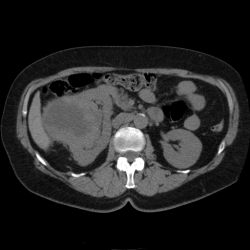

поступает женщина. Гематурия. По УЗИ - образование почки.Делаю КТ с фазным контрастированием.Вроде всё ясно, пишу ПКР правой почки. Однозначно нефрэктомия. Смотрим распространенность процесса

Пациентка 64 лет, обратилась с жалобами на болезненность в мезогастральной области, по данному УЗИ абдоминальное: объемное образование правой почки.